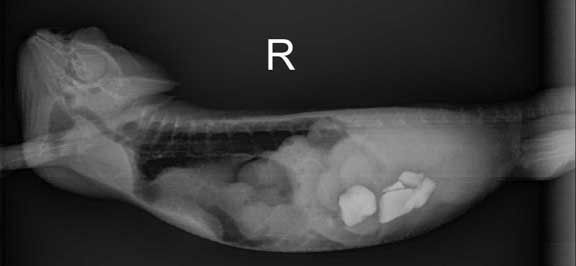

Snake with eggs